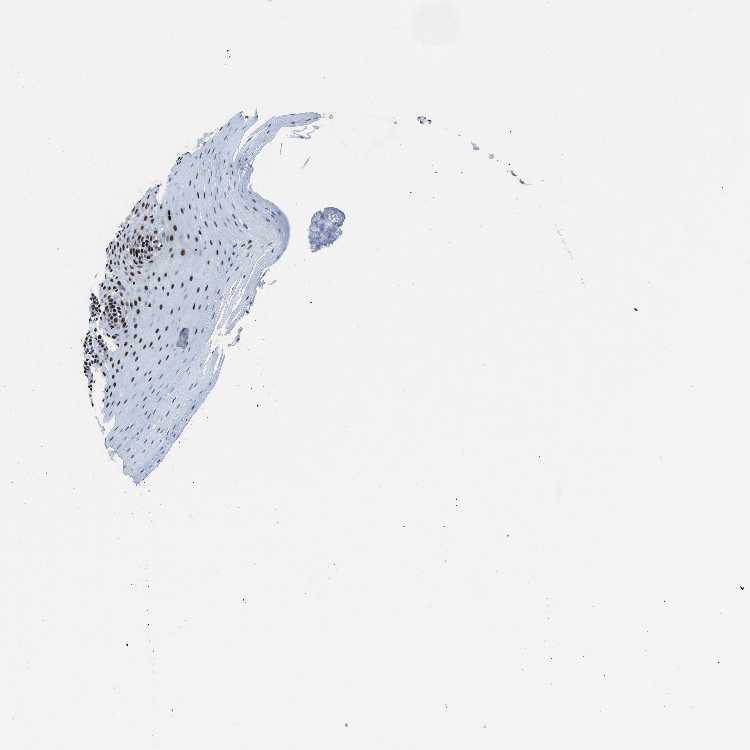

TISSUE PRIMARY DATA ORAL MUCOSA Show tissue menu

ORAL MUCOSA - Antibody stainingi

Antibody staining in the annotated cell types in the current human tissue is reported as not detected, low, medium, or high, based on conventional immunohistochemistry profiling in selected tissues. This score is based on the combination of the staining intensity and fraction of stained cells.

Each image is clickable and will lead to virtual microscopy that enables deeper exploration of all samples and also displays staining intensity scores, fraction scores and subcellular localization as well as patient and tissue information for each sample.

Antibody HPA061593Antibody CAB016327

Squamous epithelial cells MediumMedium